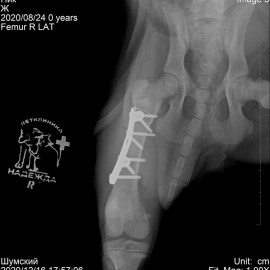

В нашу клинику обратились с жалобами на хромоту на правую заднюю лапу. После проведённых исследований был поставлен диагноз: перелом правой бедренной кости. Была проведена операция - остеосинтез правой бедренной кости.

Снимок 2-3 после операции